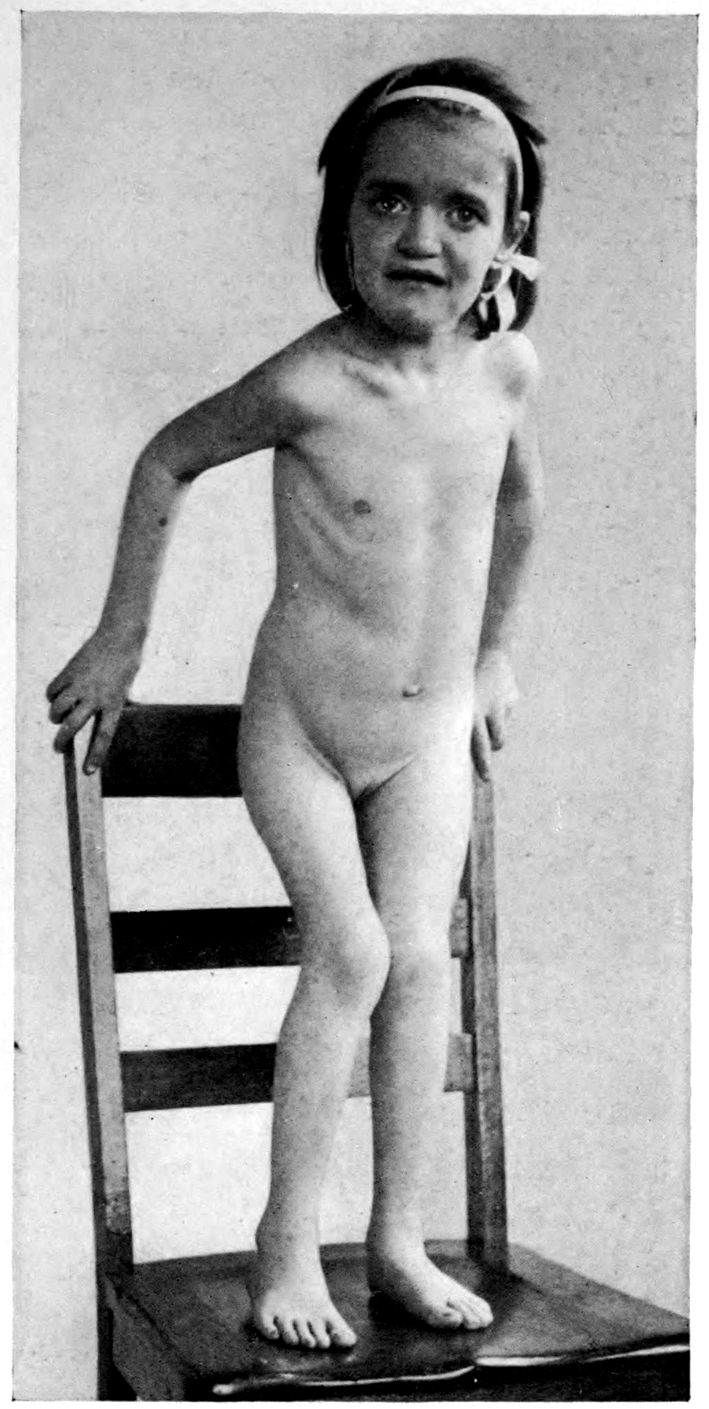

JUVENILE PARETIC NEUROSYPHILIS (“juvenile paresis”). Autopsy.

Case 5. John Lawrence was an under-sized negro, who came under hospital observation when he was 23 years of age. There was some evidence that the patient’s father was a neurosyphilitic although accurate data were out of the question. At all events, John had Hutchinsonian teeth, a forward bowing of the tibiae, and Argyll-Robertson pupils. These findings together with a history of backwardness at school seem to stamp the diagnosis. It seems that there had been a change for the worse from the age of 18, though the boy had been able to sell newspapers and black shoes up to within a year of his arrival at the hospital. During the last months of his life, he showed a general incoördination, with false movements suggesting those of a drunken person. There were numerous tremors, the glance was shifting, and there was a tendency to nystagmus. Some of these phenomena (taking into account that the Hutchinsonian teeth were not entirely typical and there was even at times some doubt as to whether the pupils were actually stiff) led to a question of the diagnosis multiple sclerosis.

There was, however, little doubt that the case was one of juvenile paresis. Among the symptoms found at various times in this case are the following: disorientation for time, place and persons, confusion, with coarsely irrelevant replies to questions, ill-defined and transitory delusions of persecution, auditory, tactile, and visual hallucinations, and defective memory.

Early in life, the patient had had a habit of falling asleep in school hours, and had experienced a number of falls at various times. During an attack of measles he had had a number of spasms, each of which lasted ten minutes or more.

The autopsy showed death to be due to an early bronchial pneumonia. The thymus was persistent, measuring 3 × 2 × .5 cm. The marrow of the femur was red.

46There was a moderate degree of sclerosis of the aorta confined to a few plaques in the arch (not a characteristic syphilitic scarring of the aorta). The spleen was small and had a thickened capsule.

The majority of the lesions, however, were in the nervous system, and the following description is taken from the routine hospital records to exemplify the findings in a fairly characteristic case of Juvenile Paresis.

Head: Scalp closely adherent to calvarium. Calvarium heavy without diploë. Dura adherent to calvarium in bregmatic region. Sinuses contain liquid blood. Arachnoidal villi in considerable quantity. Pia mater contains considerable clear fluid and shows diffuse haziness and focal thickenings. The diffuse haziness is almost universal and is best marked over the superior surface of the cerebellum. The focal thickenings are of general distribution over the veins of the sulci on the superior surface of the brim and are heaped up to form considerable linear mounds near the region of the arachnoidal villi. The superior surface of the cerebellum is traversed by similar linear mounds of fibrous tissue running at an angle to the laminæ. There is no notable increase of fibrous tissue at the base.

Brain: Weight 965 grams. The sulcation is roughly symmetrical except in the occipital poles where there is unusually rich and complex but shallow sulcation. The cortical substance is everywhere firmer than normal, but the sulci fail to flare notably. In a few places there is a focal increase of consistence of still greater degree with apparent local hypertrophy (or gliosis with increase of substance). These foci are in the right second temporal gyrus (3 cm. in diameter) and in the left first temporal gyrus (of same size but somewhat less firm) and are of a whitish, waxen appearance, being visible several feet away by reason of their color and apparent encroachment upon the adjacent sulci. The foci are sharply limited by the sulci laterally, but pale out gradually before and behind.

The convolutions of the vertex show another type of lesion. The tissue of the greater part of the vertex resembles that of the flanks and base in being firmer than normal and of a grayish pink color. Behind the fissure of Rolando on the right side and behind the anterior limits of the ascending frontal region on the left 47side the brain tissue of the vertex becomes suddenly still firmer and of a yellowish gray color. This lesion disappears gradually into the occipital microgyria behind and the gyri gradually lose their yellowish tint. The lesion fades away gradually so that it fails to involve the temporal convolutions.

The cerebral tissue cuts firmly and smoothly. The tissue of the frontal region is a little edematous. The white matter is of a normal appearance. The ependyma of all the ventricles is somewhat sanded. The fourth ventricle is most affected.

The cerebellum is not edematous and is as firm as the normal olivary bodies. The cerebellar hemispheres are symmetrical and of a normal appearance, save that the laminæ are slightly narrower than usual and very compactly set. The color, where not obscured by the haziness of the pia mater, is of a grayish pink somewhat suggestive of freshly tanned shoe leather. The substance cuts smoothly and firmly. The dentate nuclei are unusually firm. The pons is small, but of the usual color. Lower structures normal except the cord which is small and shows curious deviations from the normal markings. The posterior horns and gray commissure are at many levels the only structures to preserve the normal gray appearance, so that the H or butterfly appearance is replaced by a crescent. At these levels, traces of gray matter often stand out in the loci of the anterior horns.

The important anatomical diagnoses in the nervous system are as follows:

Atrophy of cerebrum, 965 grams (there is of course a question whether we are not dealing with a degree of cerebral hypoplasia).

Focal scleroses of cerebrum, suggesting the tuberous scleroses of Bourneville.

Occipital microgyria.

Cerebral and cerebellar gliosis.

Chronic ependymitis.

Gliosis of the gray matter of the spinal cord.

Chronic diffuse and focal leptomeningitis.

The microscopic examination confirmed the diagnosis of paresis. The hypertrophic nodules were of special interest. 48They were found to be overlain by a characteristic though thin exudate of lymphocytes and plasma cells, together with pigmented cells. The nodules appeared to be supplied with an unusual number of vessels of small calibre, about which were a few lymphocytes. The large vessels and those with well developed adventitiæ were surrounded by more numerous lymphocytes and by more focal accumulations of pigmented cells. The cortex in the middle of a nodule had almost lost its characteristic cortical layering. The cortex was here reduced (specimen from temporal lobe) to about one-quarter of its normal thickness, and was found to be composed largely of expanded neuroglia cells and vascular tissue, with a few nerve elements, small, shrunken, and dark-staining. The destructive process appeared to have borne hardest on the layer of internal large pyramids and the fusiform layer. There was, however, nowhere any evidence of focal necrosis such as ought to characterize a true gumma. The sections stained by the Marchi method failed to show evidence of fatty degeneration within the focus, although there was a marked diffuse accumulation of fatty granulations along the nerve fibres in the underlying white matter. A special study of the cerebellar material was made by one of the authors.[4] Occasional Purkinje cells showed the characteristic binucleate condition, which has frequently been noted in recent literature.

The cerebellum of this case was perhaps the most markedly diseased of all portions of the nervous system. As noted, the cerebellar tissue was exceedingly firm. How far the notable incoördination of the case (he was observed on staff rounds characteristically curled up in a heap, showing quite an unusual degree of general incoördination) was due to the cerebellar lesions, it is perhaps not possible to say.

Summary: John Lawrence, Juvenile Paretic Neurosyphilis, is a foil to Case 3 (James Dixon), paretic neurosyphilis due to acquired syphilis.

Both showed Cerebral Atrophy, but Lawrence the more 49markedly because of hypoplasia incidental to the congenital origin of his condition.

Whereas Dixon gave little or no sign of stigmata, Lawrence (besides being under-sized, having suspicious teeth, and showing at autopsy a persistent thymus) showed a Hydromyelia and curious trefoil shape to the spinal cord. Dixon on the other hand had liver lesions and arterial lesions of the leg.

The suggestion of Tuberous Sclerosis in Lawrence is not found in Dixon; but we have not found it elsewhere. Bourneville did not describe tuberous sclerosis as syphilitic.

Binucleate Purkinje cells emphasize the congenital source of the lesions in Lawrence.